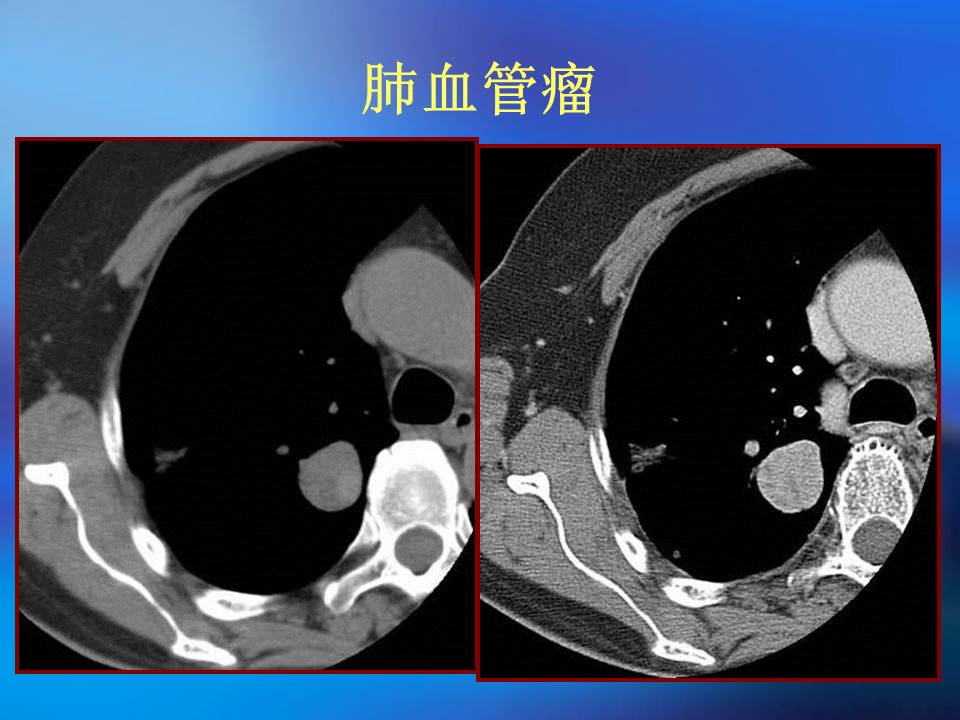

幻灯片4